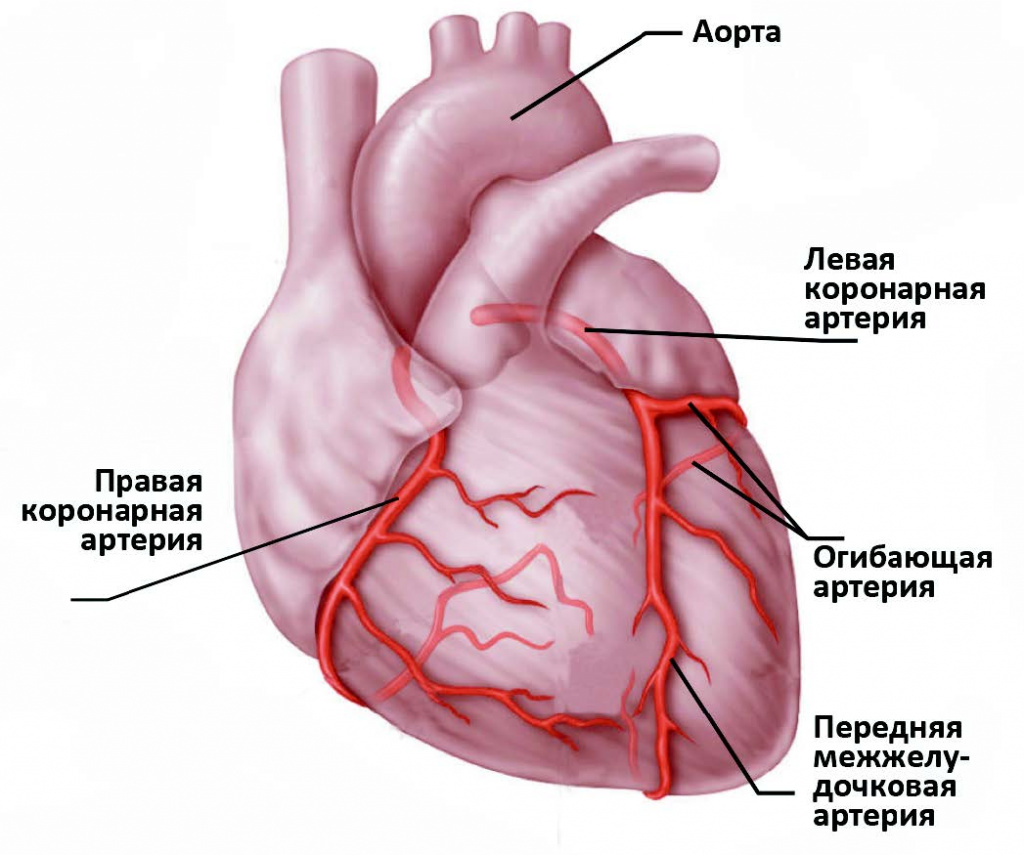

Анатомия коронарных артерий: КТ-изображения